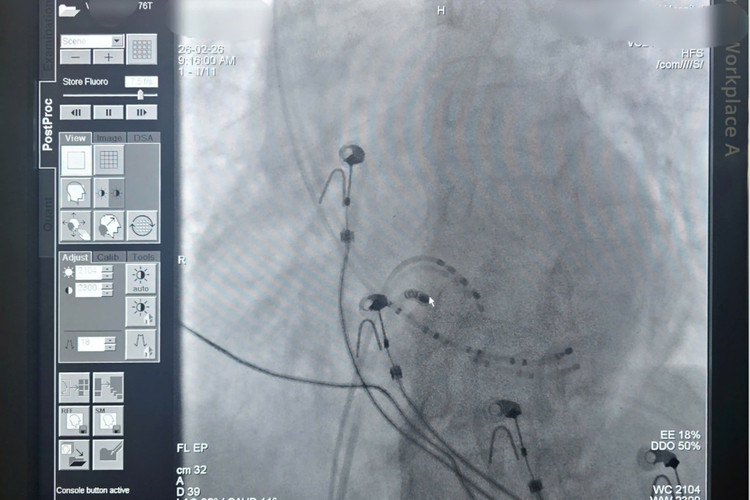

Vì vậy, các bác sĩ tim mạch can thiệp về nhịp quyết định làm thăm dò điện sinh lý buồng tim, xác định chính xác cơ chế gây cơn nhịp nhanh... sau đó đốt triệt thành công ổ rối loạn nhịp bằng sóng cao tần. Ca can thiệp diễn ra an toàn, không biến chứng. Nhịp tim bệnh nhân ổn định ngay sau can thiệp, huyết động cải thiện rõ rệt, nguy cơ tái phát được kiểm soát lâu dài.

nhip-tim.jpg

Vị trí đích triệt đốt RF thành công cơn tim nhanh.